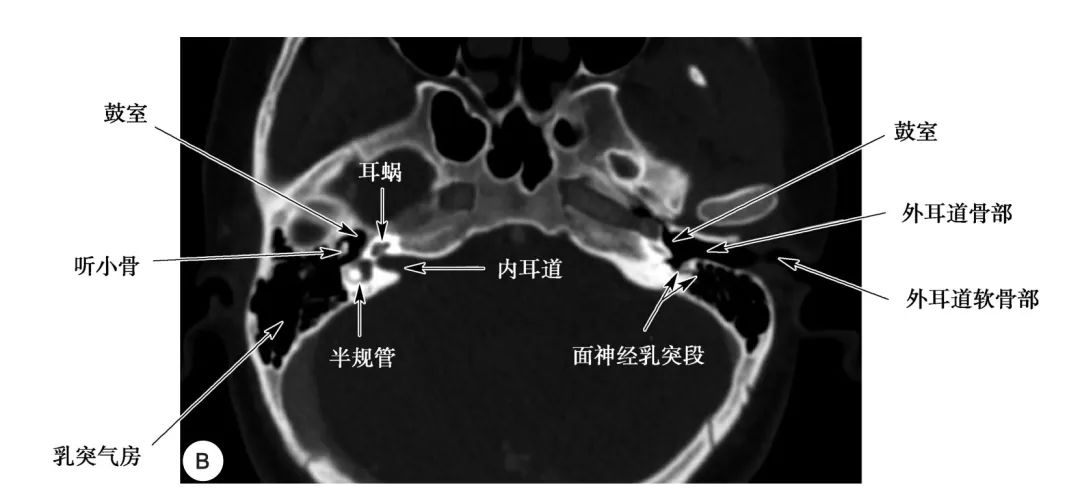

耳部及其周围的重要解剖结构 (CT横断面)

A.上骨半规管层面;B.外骨半规管层面;C.前庭窗层面;D.耳蜗层面;E.颈动脉管层面1.上骨半规管;2.弓形下窝;3.总骨脚;4.后骨半规管;5.外骨半规管;6.内耳道;7.耳蜗;8.面神经管迷路段;9.膝状神经节;10.前庭;11.上鼓室;12.乳突窦入口;13.乳突窦;14.鼓膜张肌;15.锤骨头;16.砧骨体;17.前庭窗;18.前庭导水管;19.圆窗;20.鼓岬;21.锤骨颈;22.砧骨长脚;23.面神经隐窝;24.锥隆起;25.鼓室窦;26.颈动脉管;27.咽鼓管;28.耳蜗导水管;29.颈静脉球

外耳道结构

(CT横断面)